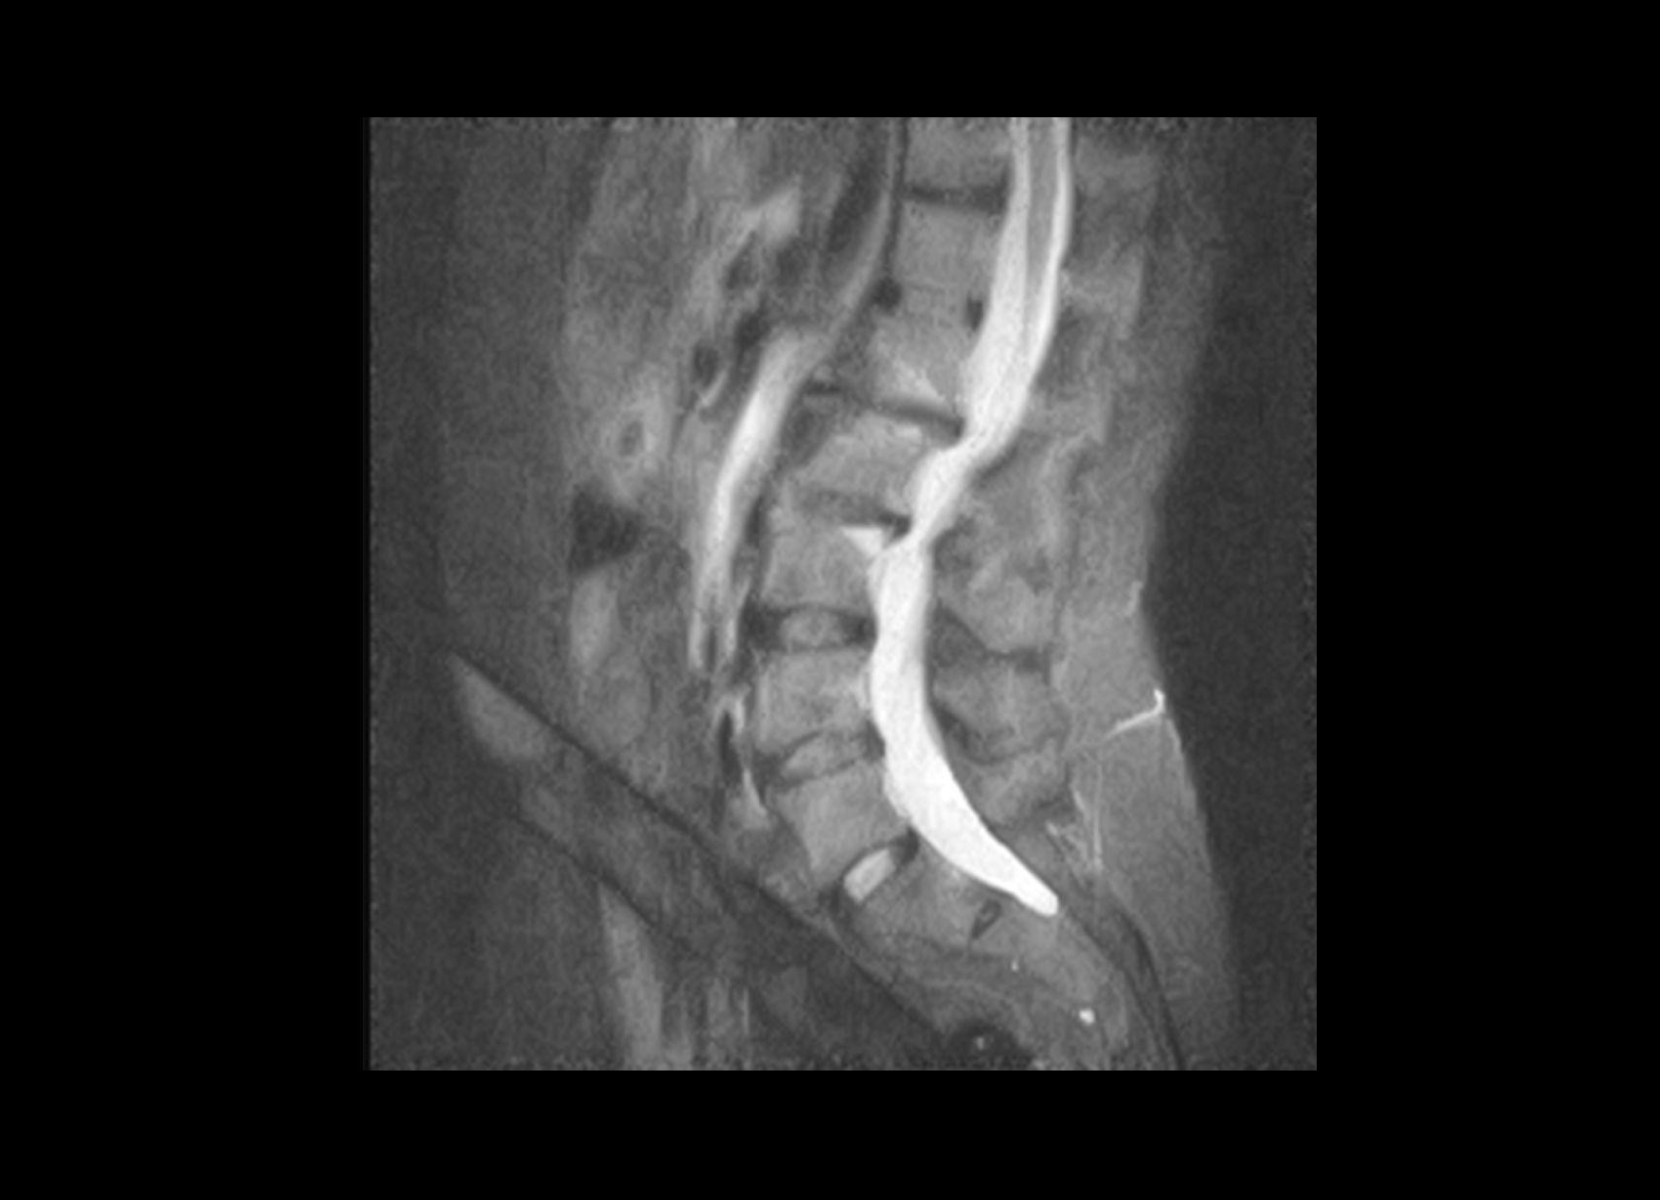

Conventional

STIR

SubtleSYNTH™

(Synthesized STIR)™

Trauma

GE 1.5T

C-spine